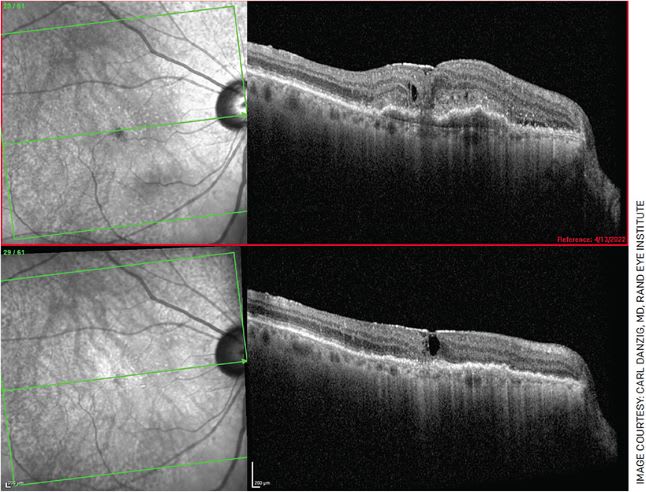

FIGURE 1. A 76-year-old female who complained of new-onset blurry vision for 3 weeks, presented with 20/200 vision in her right eye with CME, SRF, PED and subretinal hyperreflective material (top). She received Vabysmo in her right eye and, 1 month later, had remarkable anatomical improvement (bottom). However, her vision only improved to 20/100. She has been re-dosed, and we are waiting for her next follow-up visit with hope of further improvement.